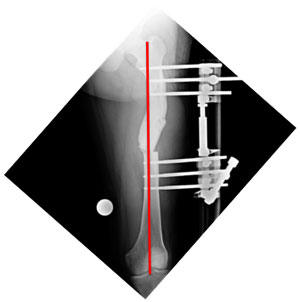

| The x-ray after surgery showing correction of axis. |